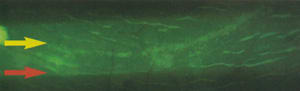

The lens edge constantly irritates the conjunctival epithelial tissue and consequently increases the conjunctival epithelial cell production or redistributes the epithelial cells. We typically observe what we believe is a raised ridge of hyperplastic conjunctival epithelial tissue. However, we often see flaps (Figure 5, red arrow) outside of the areas with CLICS (yellow arrow). Some lens decentration during eye closure may explain this.

Figure 5. A

conjunctival epithelial flap (red arrow) located outside

of the area with CLICS (yellow arrow). |